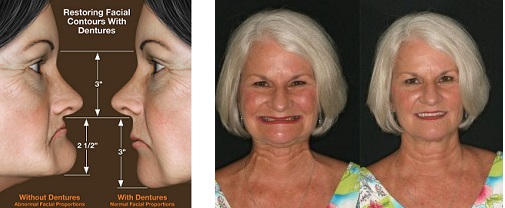

When the natural teeth are lost, the surrounding bone loses its role of supporting them and the body starts to resorb it as useless. The lack of stimulation provided by the teeth roots can lead to massive bone loss in the jaws, seriously affecting facial integrity and appearance. Dentures start to not fit well and have to be replaced or repaired every few years. Implants act as the teeth roots continuing to stimulate the bone cells and help the jawbone around them to stop deteriorating. If enough denture implants are used they can help the jawbone structures to remain healthy and intact.

For personal satisfaction, this is often the ultimate test – how will I look? As a product of the evolving art of facial aesthetics, removable dentures supported by implants can replace lost tissues and restore balance to the face, and often produce a remarkable smile “makeover.”